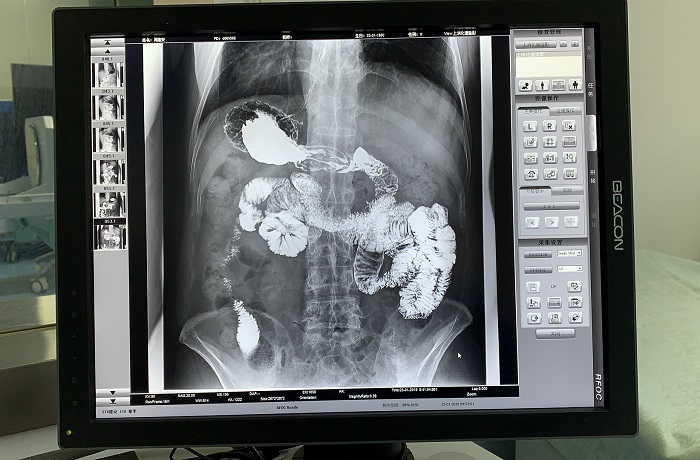

胃腸道造影高清影像